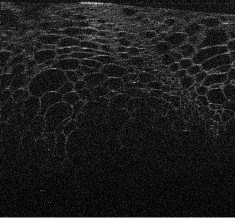

Visualizations of cross sectional reconstructions from the sub-sampled measurements are shown in Figure 2 and Figure 3 for the beaded gel and cucumber tissue samples respectively. Quantitative results of the NCC are then shown in Table 1.

From Figure 2, it appears that enhancement of the image structure is improved in each instance of MBIR. Random sub-sampling results in the best preservation of structure, followed by equispaced, and finally partial, which exhibits strong artifacts in each case. TV regularization appears to reasonably robust, but exhibits some block-like image artifacts, whilst DT-CWT has better preservation of speckle structure.